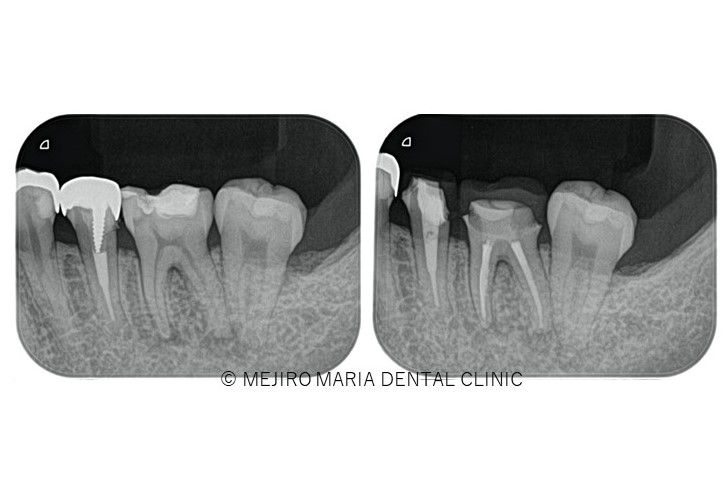

東京 目白マリア歯科 精密根管治療の症例

【初回根管治療(抜髄)神経をとる

治療】

初めて歯の神経(歯髄)を取り除く処置です。歯髄炎の症状は抜髄処置を施すことで改善されます。また、根管内の細菌感染が再根管治療よりはまだ少ないので、治療の成功率が高い時期でもあります。根尖性歯周炎の罹患を最小限にすると同時に再根管治療を不要にすることで将来的に歯を最大限保存することにつながるため、再根管治療に比べると精密根管治療の費用対効果が高くなります。

【再根管治療(感染根管治療)】

感染した歯髄や腐敗物、細菌を取り除く治療

再根管治療とは、過去に行った根管治療のやり直しを行う処置です。根尖性歯周炎の原因は根管内に潜む細菌感染ですので、根管内の細菌数を無菌的環境下で減少させ、密に封鎖することで予知性を高めることが可能です。